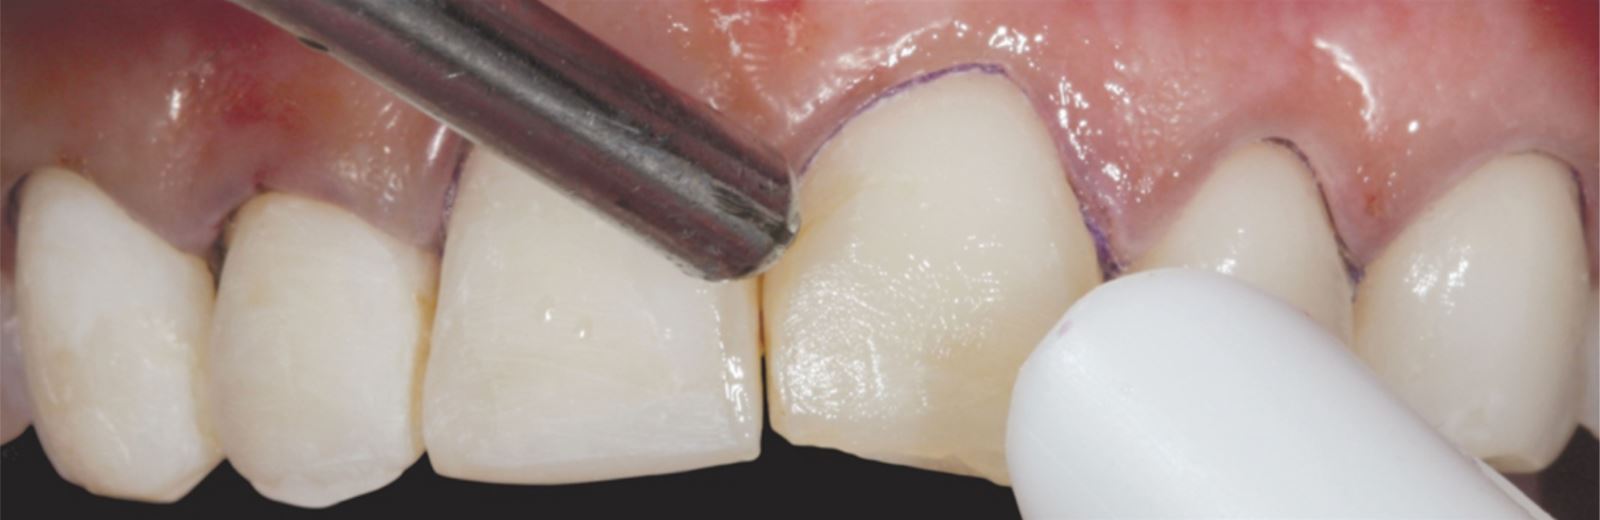

Příprava sulku:

Do gingiválního sulku byla vložena pletená retrakční vlákna Ultrapak™ velikosti #0 k přípravě pro leptání.

Leptání nepreparované skloviny:

Nepreparovaná sklovina byla leptána 35% kyselinou fosforečnou Ultra-Etch po dobu 30 sekund.